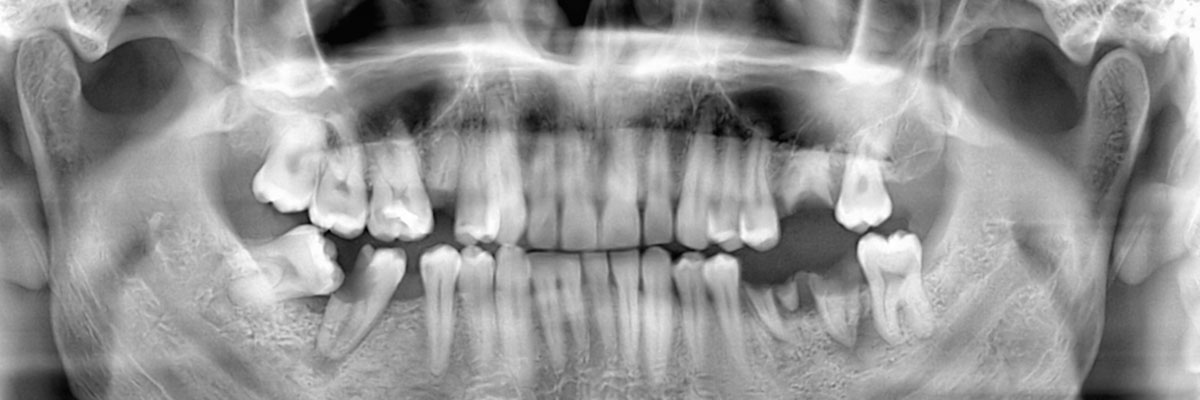

You may need a wisdom teeth extraction at some point in your life. It is rare for a person to have enough room for all of their wisdom teeth, and as a result, they tend to grow in impacted. This can be uncomfortable, pushing your other teeth forward and creating a space for food to become trapped; it can also increase your risk of infection and decay. This is why we often recommend that our patients have their wisdom teeth removed. When you schedule an appointment with Schommer Dental, we can examine you, take X-rays, and let you know if and when you should schedule an extraction procedure. You can reach us by calling (563) 272-2331.

This is a dental procedure where your wisdom teeth are removed. How they are removed will be based on their current location and whether or not they are impacted.

If your wisdom teeth have grown in straight, removing them is fairly easy. In this case, you would visit a dentist to have them pulled out using dental tools. Most likely, no surgery would be required. However, if your teeth are impacted, the procedure requires oral surgery. In order to access the actual tooth, the gum tissue covering it will need to be cut open. After numbing the area, a flap will be created in the gum tissue. This allows the dentist or oral surgeon to view the tooth. If muscle or bone is covering it, that will also need to be cut away to provide clear access to the actual tooth. At this point, your dentist may be able to grab the tooth and simply lift it out of the socket. If, however, it does not budge when being wiggled, then the actual tooth will need to be broken into several pieces that can be extracted individually.

At Schommer Dental, we understand that each of our patients is unique and so are their teeth. Whether or not you need to have your wisdom teeth removed by a dentist, will really depend on the size of your palate. If you have plenty of room for all of your teeth and your third molars, they can stay in place. There is no point in removing something that grows in straight and is healthy. However, any tooth that grows in impacted needs to be removed because it is posing a direct threat to your other teeth and roots in addition to being a target for infections. The best way to find out if your wisdom teeth should be removed is to call 563-272-2331 and schedule an appointment with our Davenport dentist office. We can make a recommendation and answer any other questions you have about the procedure itself.